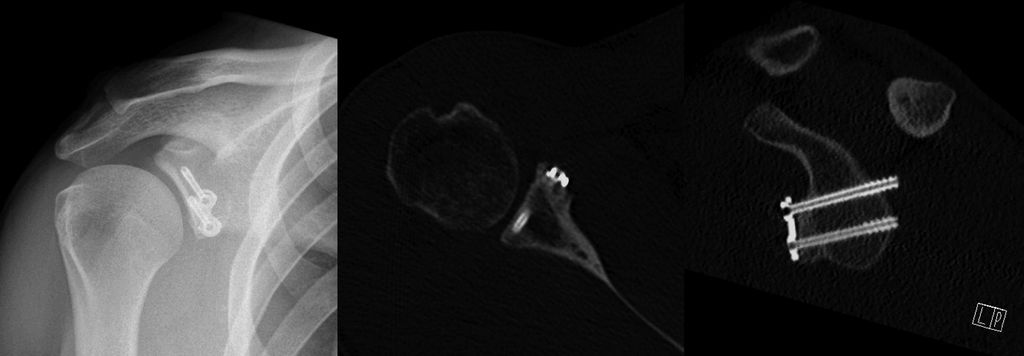

Der Korakoidtransfer nach Latarjet weist als Primäreingriff hinsichtlich der postoperativen glenohumeralen Instabilität im Vergleich zum arthroskopischen Bankartrepair bessere Ergebnisse auf.64 Die Versetzung des Korakoids an den vorderen Pfannenrand führt nicht nur zu einer Erweiterung der knöchernen Gelenkspfanne, sondern durch den Sling-Effekt der anhaftenden Conjoint-Sehnen bietet das Verfahren einen zusätzlichen stabilisierenden Effekt bei Abduktion-Außenrotation (Abb. 5a–c). Das Latarjetverfahren weist im Vergleich zum arthroskopischen Bankartverfahren sehr gute Langzeitergebnisse mit sehr guten Funktionsscores auf.64–68 Es zeichnet sich durch geringe Reluxationsraten (0–6%) aus.69–71 Auch in einer sehr aktiven jungen Patientengruppe (Alter 25,2/26,4 Jahre) mit nur subkritischem Knochendefekt konnten bessere Funktionsscores und geringere Reluxationsraten mit dem Latarjetverfahren erreicht werden. Im Gegensatz dazu zeigten signifikant mehr Patienten nach arthroskopischem Bankart eine permanente physische Einschränkung.72,73

Abb. 5a–c: Die Versetzung des Korakoids an den vorderen Pfannenrand führt nicht nur zu einer Erweiterung der knöchernen Gelenkspfanne, sondern durch den Sling-Effekt der anhaftenden Conjoint-Sehnen bietet das Verfahren einen zusätzlichen stabilisierenden Effekt bei Abduktion-Außenrotation

Auch in der Revisionssituation nach fehlgeschlagener arthroskopischer Bankartoperation ist meist eine Knochenblockoperation zielführend. Die klinischen Ergebnisse mit dem Latarjetverfahren als Revisionseingriff sind sehr gut und signifikant besser als mit einer neuerlichen arthroskopischen Bankartoperation, wenngleich sie schlechter sind als nach primären Latarjetoperationen.25 Die Angaben in der Literatur hierzu sind allerdings uneinheitlich. Während in einigen Studien bis zu doppelt so viele Rezidivinstabilitäten gefunden wurden,74,75 geben andere Autoren keinen signifikanten Unterschied im klinischen Outcome, in der Reluxationsrate sowie der „Return to sports“-Rate an.63,76,77 Im Vergleich zur arthroskopischen Bankartoperation sind die Reluxationsraten allerdings deutlich geringer.66,78

In den letzten Jahren wurden auch arthroskopische Latarjetverfahren entwickelt.79,80 Calvo konnte in seinem Patientenkollektiv mit arthroskopischen Latarjetoperationen ein etwas besseres klinisches Ergebnis und eine etwas geringere Reluxationsrate bei Primäreingriffen gegenüber den Revisionseingriffen feststellen.65 Auch nach 5 Jahren bleibt die Reluxationsrate bzw. die Rate neuerlicher Instabilität niedrig (1,59%).81